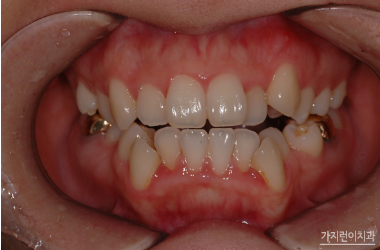

덧니 치아교정은 심각도에 따라 교정시기를 차별화해야 하는데요. 벗어난 정도가 심하지 않다면 시작 시기가 중요하지 않지만 심한 경우에는 초등학교때 시작하는 게 좋습니다. 최근에는 교정 술기의 진화로 인해 다양한 교정장치를 만나볼 수 있게 되었는데요. 금속, 세라믹, 플라스틱 등 다양하지만 각 장치별로 기능 차이가 있기 때문에 교정과 담당원장님과 상의 후 결정해보는 게 좋겠습니다.

한마디로 덧니교정은 성장기에 진행해도 좋지만 성인이 된 이후에도 받아볼 수 있는데요. 덧니로 인해 불편함이나 구강질환이 걱정된다면 바로 치아교정을 시작하는 게 좋겠습니다. 덧니 교정이라고 해서 부분교정으로만 극복할 수 있는 것은 아닌데요. 덧니 형태와 전체적인 치열 상태를 확인한 후 구강 구조와 골격 등을 살펴 플랜을 수립해야 하겠습니다.